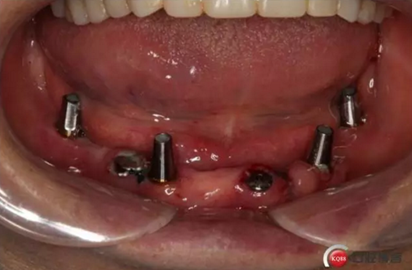

2)術(shù)前準(zhǔn)備及手術(shù)過(guò)程,測(cè)量血壓及血糖,簽種植知情同意書;嚴(yán)格遵循無(wú)菌操作,局麻下采用微創(chuàng)技術(shù)于323436分別植入osstem4.0X10,4.0X10,4.5X7; 434446分別植入osstem4.0X1O,4.0X10,4.5X7.初期穩(wěn)定性均達(dá)到了35N.CM以上;嚴(yán)密縫合,止血,種植體位點(diǎn)和方向與設(shè)計(jì)一致。

4)三個(gè)月后行種植二期手術(shù)并拔除33殘冠,于34364346種植體接入成品基臺(tái),調(diào)改活動(dòng)義齒做一個(gè)改良式的套筒冠覆蓋義齒。